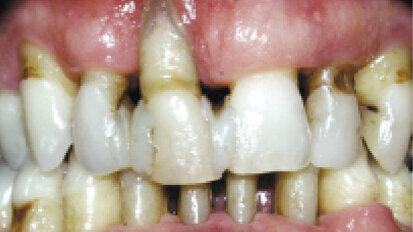

Kde končí parodontologie a nastupuje implantologie

Ošetření parodontu poskytuje nejen dobré orální zdraví, ale je také základním kamenem pro ...